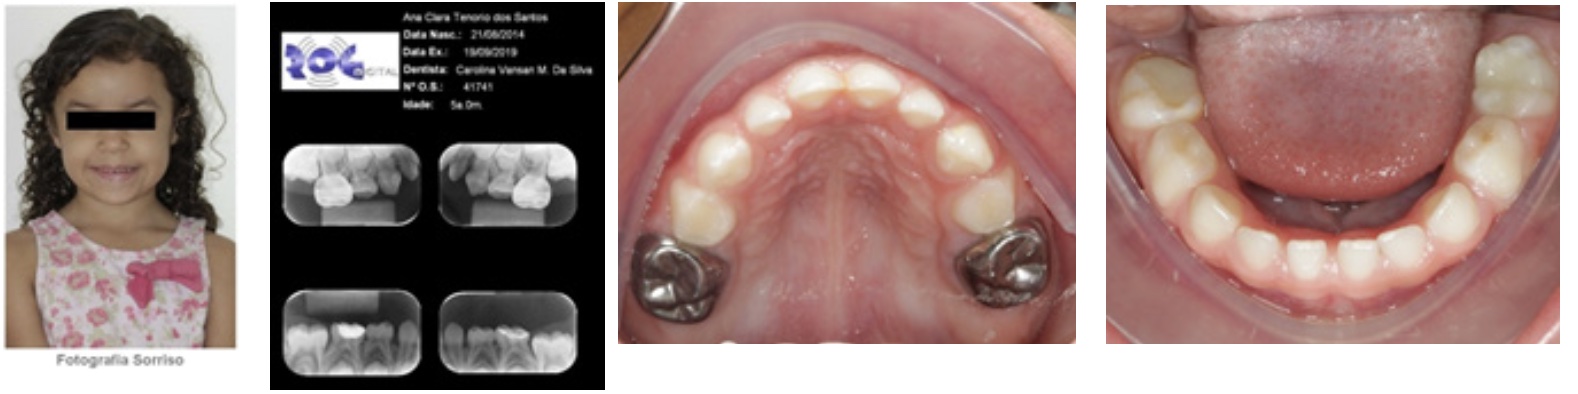

En tal sentido, la gemela 1 recibió restauraciones en los dientes 75 y 85 en resina compuesta, pues como supradicho, ya había recibido restauraciones invasivas (Figura 3). La gemela 2 recibió restauraciones ionómero en los dientes 55 y 56 a través de la filosofía de ART (Tratamiento Restaurador Atraumático). También, en el diente 75, pulpectomía y corona de acero debido la gran destrucción coronal, procedimiento que proporciona mejor preservación del tratamiento endodóntico (Figura 4). Los criterios usados para la elección del tratamiento de las niñas están basados en evidencias clínicas y científicas de la mínima intervención del tratamiento de HMD.

Figura 3: Gemela 1: Imagen clínica y radiológica sacadas al finalizar el tratamiento. Se observa: en la imagen 1, fotografía de la sonrisa; en la 2, radiografías periapicales en las cuales se ve una corona de acero en los dientes 75 y 78; en las imágenes 3 y 4 se muestra imágenes intrabucales de las caras oclusales de las arcadas inferiores y superiores. Se nota los tratamientos realizados: coronas de acero en los dientes 85 y 87, restauración con cemento de ionómero de vidrio en los dientes 55 y 65, además en los dientes 75, 85, 55 y 65 con hipomineralización.